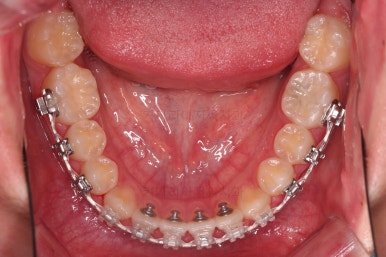

동래교정치과 초진 시 입안의 모습입니다.

치아가 벌어진 것도 벌어진 것이지만 교합이 전혀 안되고 있었어요.

틈새도 아랫니에 훨씬 많았고요.

윗니가 있는 위턱뼈가 전반적으로 아래턱에 비해 3차원으로 작은 양상이었습니다.

이번 환자분은 아랫니가 전반적으로 앞이든, 뒤든, 양옆으로든 넓어져 있는 양상이었고 그래서 아랫니에 틈도 많고 아래 앞니도 밀려나와 있는 양상인거죠.